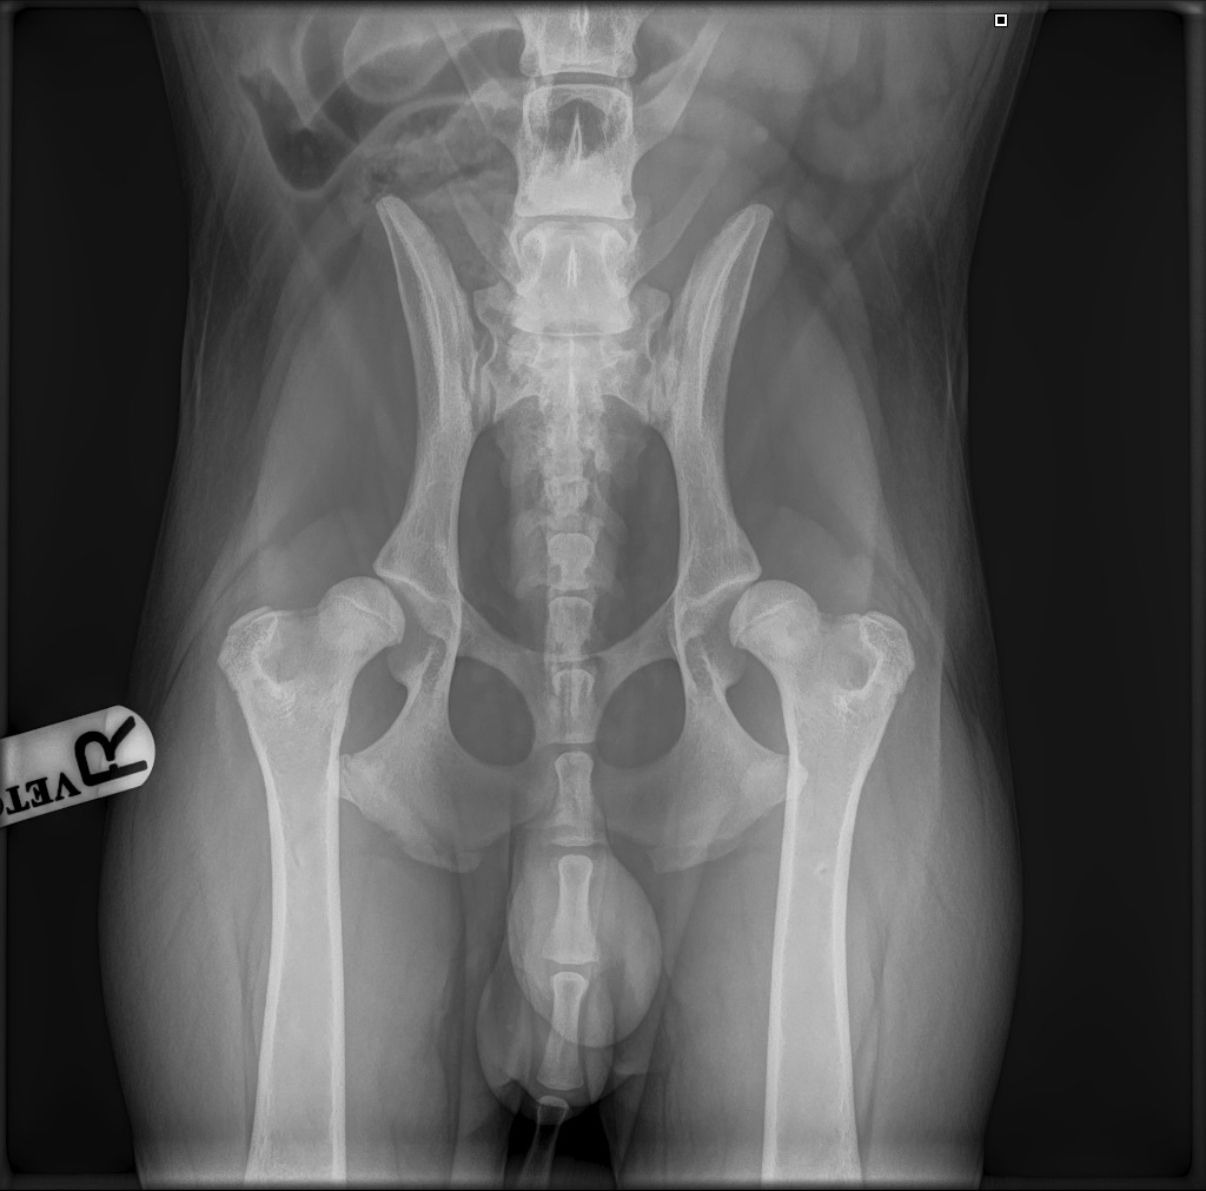

But now, Ozzy is facing his biggest challenge yet: advanced hip dysplasia in both hips.

From the start, I noticed something wasn’t quite right. Ozzy struggled to jump, cried at the top of the stairs, and hesitated to go to the toilet because of the pain. It took multiple vet visits and a lot of persistence, but we finally got the diagnosis: he’s been living in chronic pain since birth. His hips are so damaged that surgery is now the only way to give him a chance at a pain-free life.

This is the lowest cost we’ve been able to find—previous quotes were as high as £10,000–£12,000. The rescue that brought him over has already contributed all they were able to raise, which thankfully covered his X-rays (£800+), but now we're at a standstill.